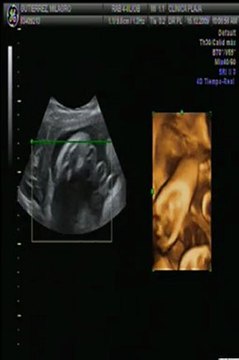

¿En qué consiste el estudio de ultrasonido transfontanelar?